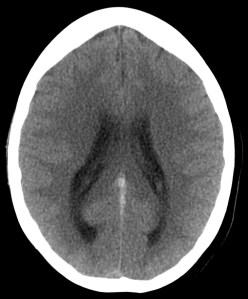

Se decide ingreso de la paciente para estudio y, ante el incremento de la cefalea y empeoramiento del estado general, se realiza nuevo TC de cráneo sin contraste. Veámos las imágenes.

1- TAC SIN CONTRASTE:

Se realiza para descartar otros procesos como infartos, tumores o infecciones.

- Signos directos: Cuerda Hiperdensa. En caso de trombo en las venas corticales, se observa el signo de la cuerda hiperdensa intraluminal. El trombo puede permancer hiperdenso 2 semanas para luego hacerse isodenso. La S y E de este signo son bajas.

- Signos indirectos: Cambios en el parénquima debido a la isquemia por perturbación del flujo venoso, produciéndose edema, infartos o hemorragias. Los infartos no hemorrágicos son las lesiones más frecuentes, suelen ser de localización subcortical, no sigue una distribución arterial y se localiza en las inmediaciones del seno afectado. Una afectación del SSS (el más frecuente) produce afectación bilateral en los territorios frontales, parietales y occipitales. Una afectación del ST afecta los lóbulos temporales. El seno recto afectado produce lesión profunda, en el tálamo. Los infartos hemorrágicos son menos frecuentes, se han descrito sangrados subdurales, subaracnoideos e incluso abiertos a ventrículos. El edema que se produce puede originar efecto masa con desplazamiento de la línea media e incluso disminución de ventrículos (dificil de valorar en jóvenes). La hidrocefalia marcada no se suele producir.